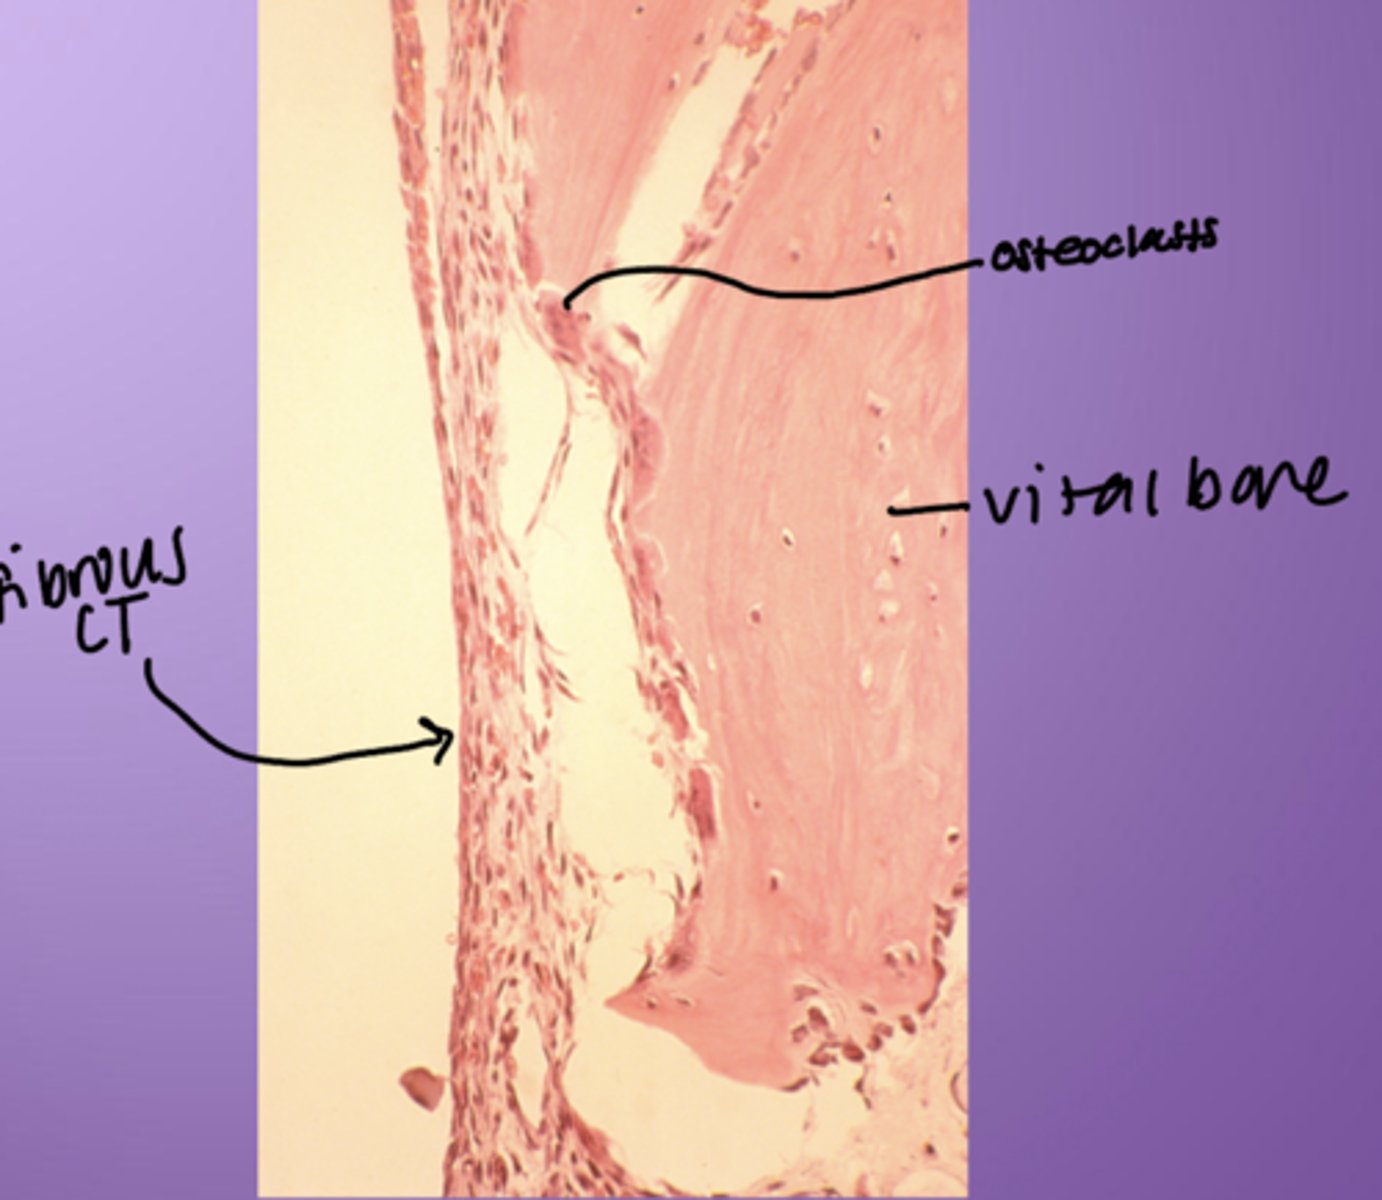

Traumatic bone cyst - histology

- Osteoclasts

- Vital bone

- Fibrous CT